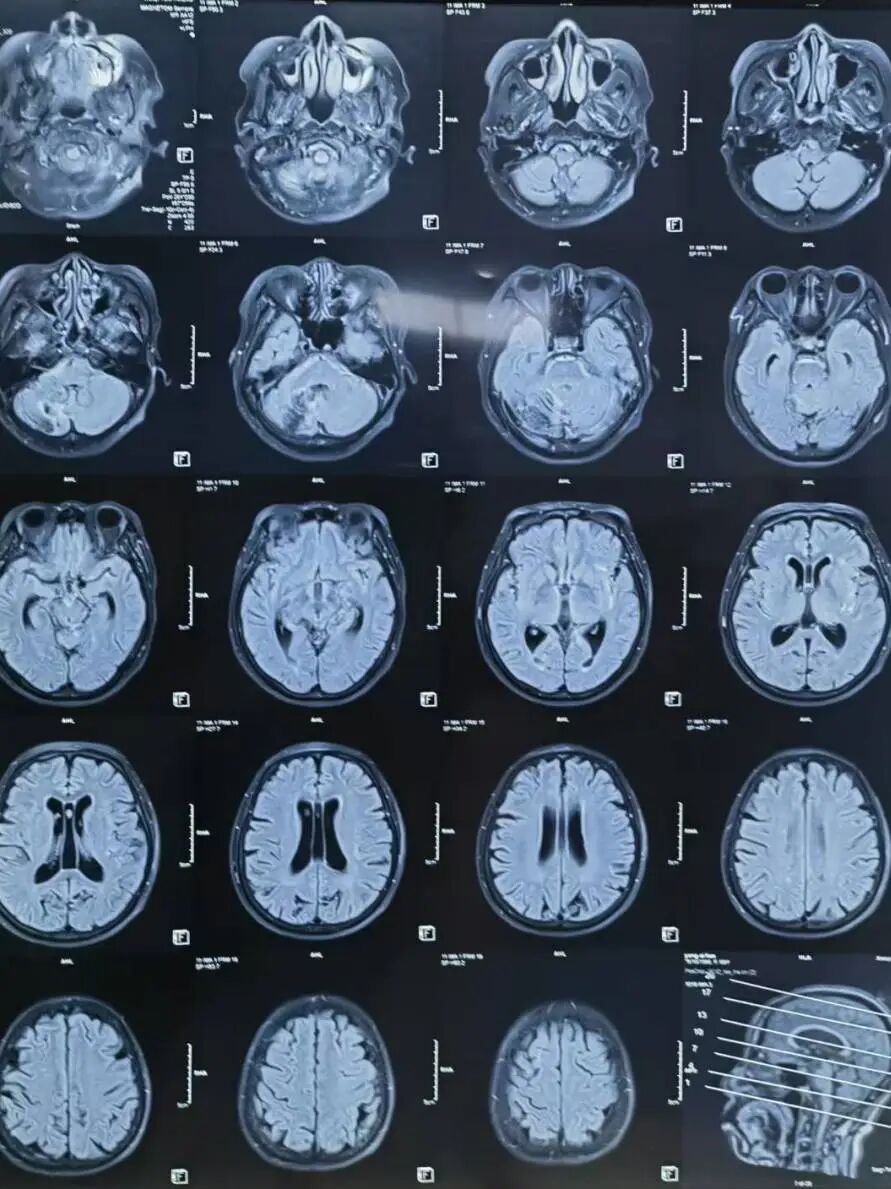

辅助检查:颅脑MR(当地医院):左侧小脑半球、双侧侧脑室旁、基底节区及双侧额叶皮层下多发腔隙性脑梗死;右侧小脑半球软化灶血管造影(当地医院)。颅脑MRA(当地医院):左侧颈内动脉后交通段局部膨大,可疑动脉瘤。 脑血管造影(当地医院) :左侧后交通动脉瘤。

颅脑MR (当地医院) :左侧小脑半球、双侧侧脑室旁、基底节区及双侧额叶皮层下多发腔隙性脑梗死;右侧小脑半球软化灶。

颅脑MRA(当地医院):左侧颈内动脉后交通段局部膨大,可疑动脉瘤。